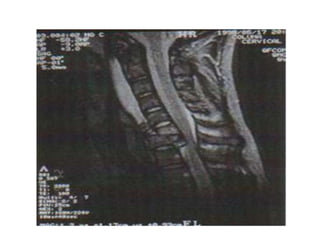

COLUNA

CERVICAL

COLUNA CERVICAL